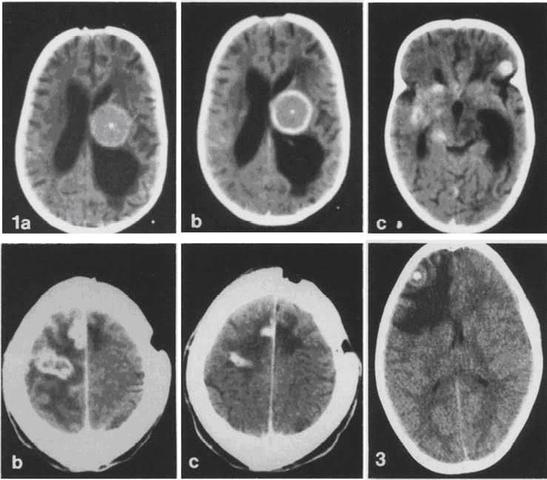

Glioblastoma multiforme divided into two groups.

The term glioblastoma multiforme was introduced in 1926 by Percival Bailey and Harvey Cushing based on the idea that the tumor originates from primitive precursors of glial cells (glioblasts), and the highly variable appearance due to the presence of necrosis, hemorrhage and cysts.

Glioblastoma multiforme, a very malignant type of brain cancer.